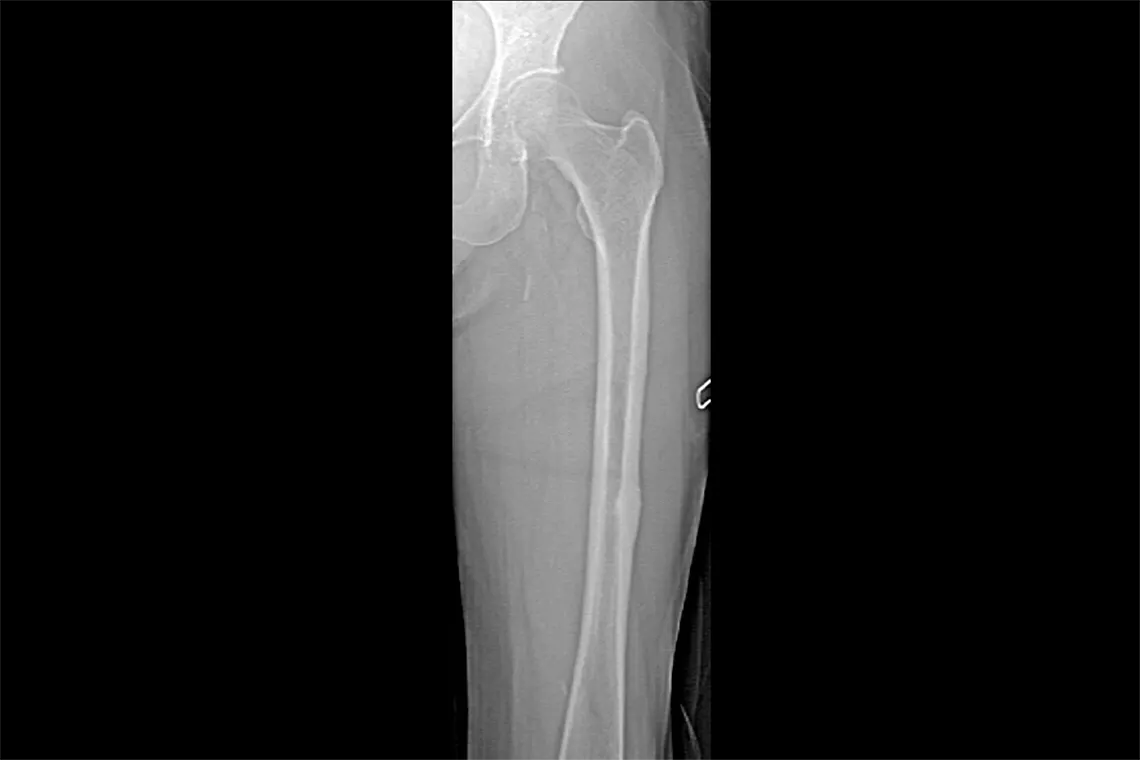

O Horizon DXA gera imagens de qualidade radiográfica de todo o fémur para a avaliação de potenciais fraturas atípicas do fémur.31 Uma radiografia rápida de 15 segundos revela um espessamento cortical do osso, fazendo com que seja fácil e rápido monitorizar os efeitos da terapia com bisfosfonatos ao longo do tempo.

Veja a placa calcificada na aorta abdominal, que pode ser um forte indicador de doenças do coração e AVC, duas das principais causas de morte em homens e mulheres.